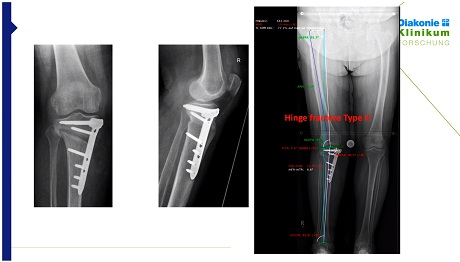

Case Reports: Typical Tibial Plateau Fractures in Ski Sports K. Tecklenburg

12 min

Recognize tibial plateau fractures as a sport specific entity in skiing